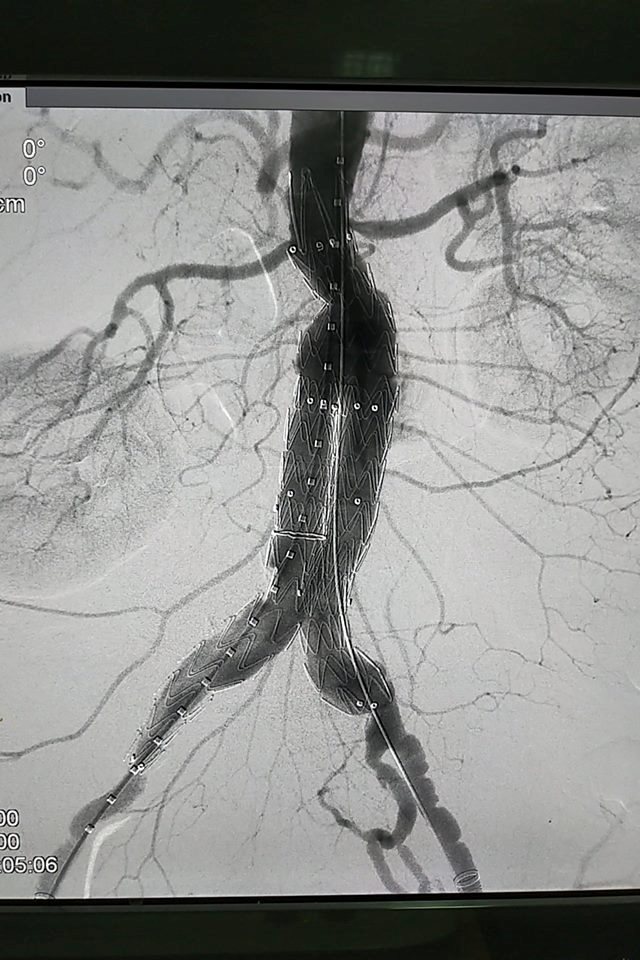

Bệnh nhân sau can thiệp đã khỏi phình

Tuy nhiên, cùng với tiến bộ của y học, đặc biệt tiến bộ của ngành tim mạch can thiệp, bệnh nhân có thể không cần phải mổ. Một phương pháp điều trị đặc biệt sẽ thay thế phương pháp mổ truyền thống, gọi là đặt ống ghép nội mạch qua da. Đây là can thiệp ít xâm lấn với kết quả ban đầu tốt.

Đặt ống ghép nội mạch là phương pháp điều trị thay thế an toàn và hiệu quả so với phương pháp phẫu thuật vì nói không sử dụng tuần hoàn ngoài cơ thể. Để đặt ống ghép nội mạch an toàn cần phải đánh giá kích thước của động mạch đầu xa làm đường dẫn có đủ hay không, đường đi của động mạch chủ có bị quặn xoắn hay bị gập góc, và quan trong nhất là hình thái học của túi phình có thích hợp hay không.

Các bác sĩ can thiệp sẽ luồn ống ghép qua da vào vùng mạch bị phình và ống ghép này sẽ thay thế đoạn mạch bệnh lý. Bệnh nhân sẽ hồi phục nhanh chóng, không cần nằm viện lâu, theo dõi chăm sóc sau can thiệp cũng nhẹ nhàng. Tuy nhiên, chi phí cho can thiệp này còn cao so với thu nhập người dân của nước ta.